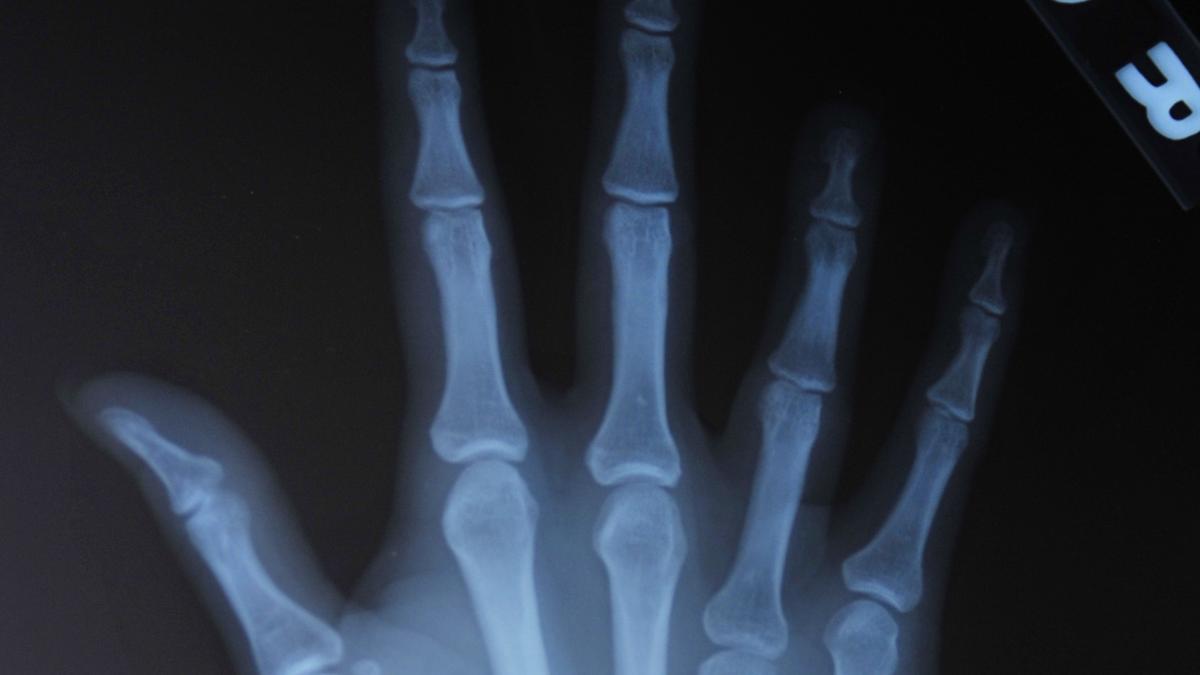

This week’s Hindu science quiz is about human bones